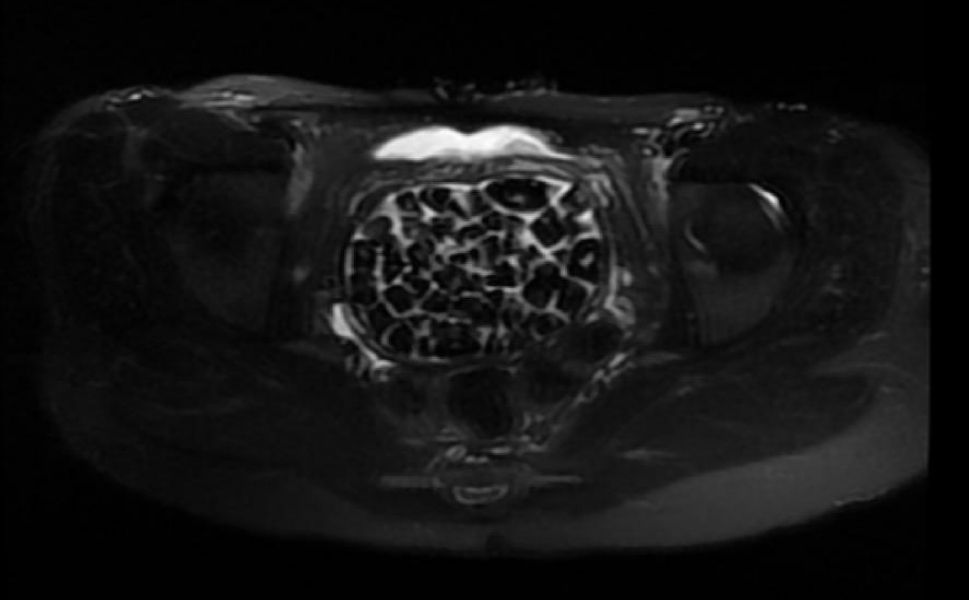

Öztürk’ün doğumdan itibaren çeşitli operasyonlar geçirdiği öğrenildi; mesanenin olması gereken bölgesinin arka yüzeyinde taşlarla dolu bir kese tespit edildi.

İdrarın vajina boşluğuna sızması sonucu burada biriken sıvı, zamanla mineral çökeltisi oluşmasına neden oldu.

11 Eylül’de Üroloji ve Jinekolojik Onkoloji ekipleri ortaklaşa yapılan ameliyatta, en büyüğü 2,5 santimetre olan taşlarla birlikte toplam 287 taş başarıyla çıkarıldı.